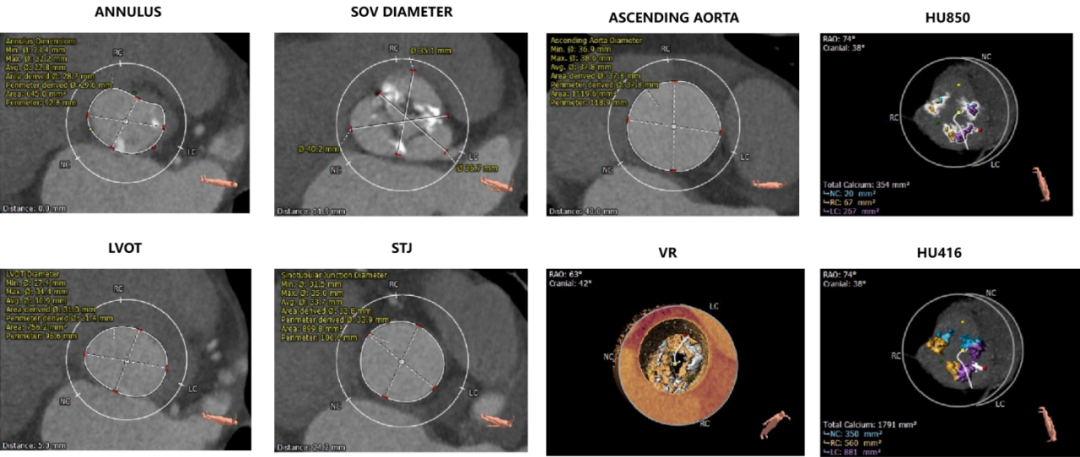

主动脉根部评估:

CT数据显示该患者为重度钙化的三叶式主动脉瓣,钙化分布集中于瓣叶边缘。

左冠开口高度12.1mm,右冠开口高度16.5mm,左侧冠脉预估存在一定遮挡风险;心室壁可见明显增厚。